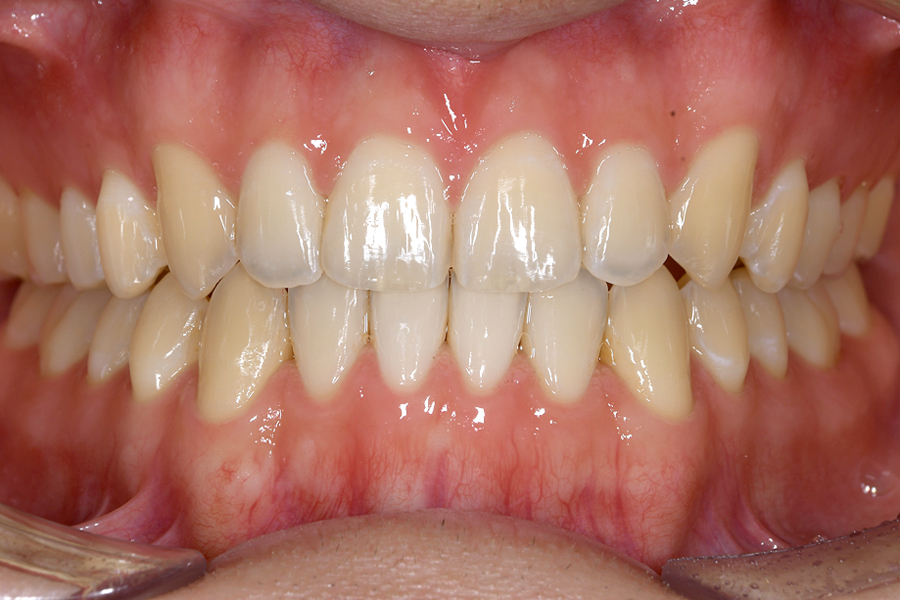

| 主訴 | 歯並びを治したい |

|---|---|

| 治療期間 | 5か月 |

| 治療費 | 部分マウスピース矯正(モニターキャンペーン)と ホワイトニングセット 422,596円(税込) |

| 治療内容 | 目立ちにくいマウスピース矯正 (非抜歯矯正) 歯と歯の間に隙間をつくることにより、歯列弓を広げながら治療を行いました。 また矯正用マウスピースをトレー代わりにし、ジェルを入れてホームホワイトニングを同時に行っております。 |

| 治療のリスク | ・後戻りする可能性があるのでリテーナーを最低でも矯正期間以上はつける必要があります。 ・ホワイトニング後、一時的に痛みが出る場合があります。 |